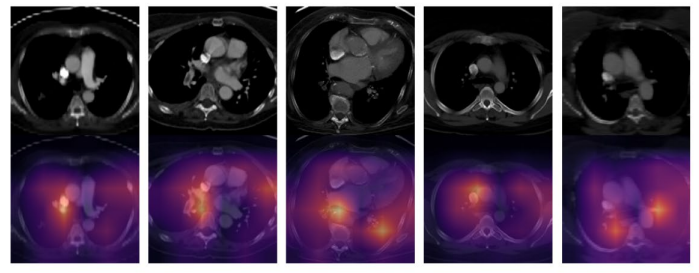

\ Figura 2. Mapas de activación de clase (CAMs). Los mapas de activación de clase (CAMs) destacan las áreas de imagen más importantes para la toma de decisiones del modelo de detección de EP.